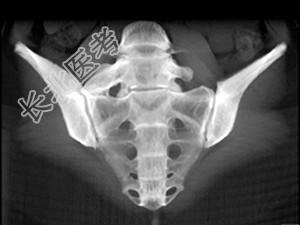

- 单项选择题男,35岁, 下腰部痛,L4-5棘突旁有明显压痛, 结合图像,最可能的诊断是 ( )

C、腰椎骶化

D、骶椎腰化